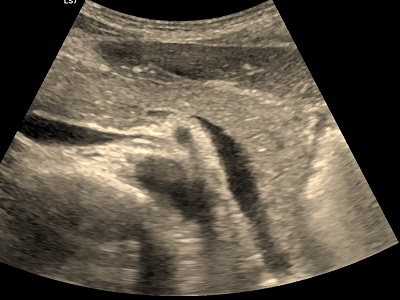

Trzustka najlepiej widoczna jest u osób szczupłych. Jeśli odległość od powłok skórnych nie przekracza 4cm można próbować ją obrazować sondą liniową o lepszej rozdzielczości.

W większości przypadków u dorosłych musi być jednak stosowana sonda konweksowa o mniejszej częstotliwości to znaczy 3-4 MHz. Z tego powodu drobne szczegóły budowy i echostruktury pozostaję niemożliwe do zobrazowania. Im głębiej położony narząd tym mniej szczegółów można zobrazować sondą 3-4 MHz.

Zmiany chorobowe widoczne są jedynie wtedy gdy mają inną echogeniczność od otaczających tkanek, to znaczy inny odcień szarości. Najlepiej widoczne są torbiele, które są po prostu bezechowe, czarne na jaśniejszym szarym tle miąższu trzustki.

Dodatkowo do przodu od trzustki położone są jelita, w których gromadzą się gazy całkowicie przesłanające narząd zwłaszcza u ludzi z nadwagą lub otyłością.